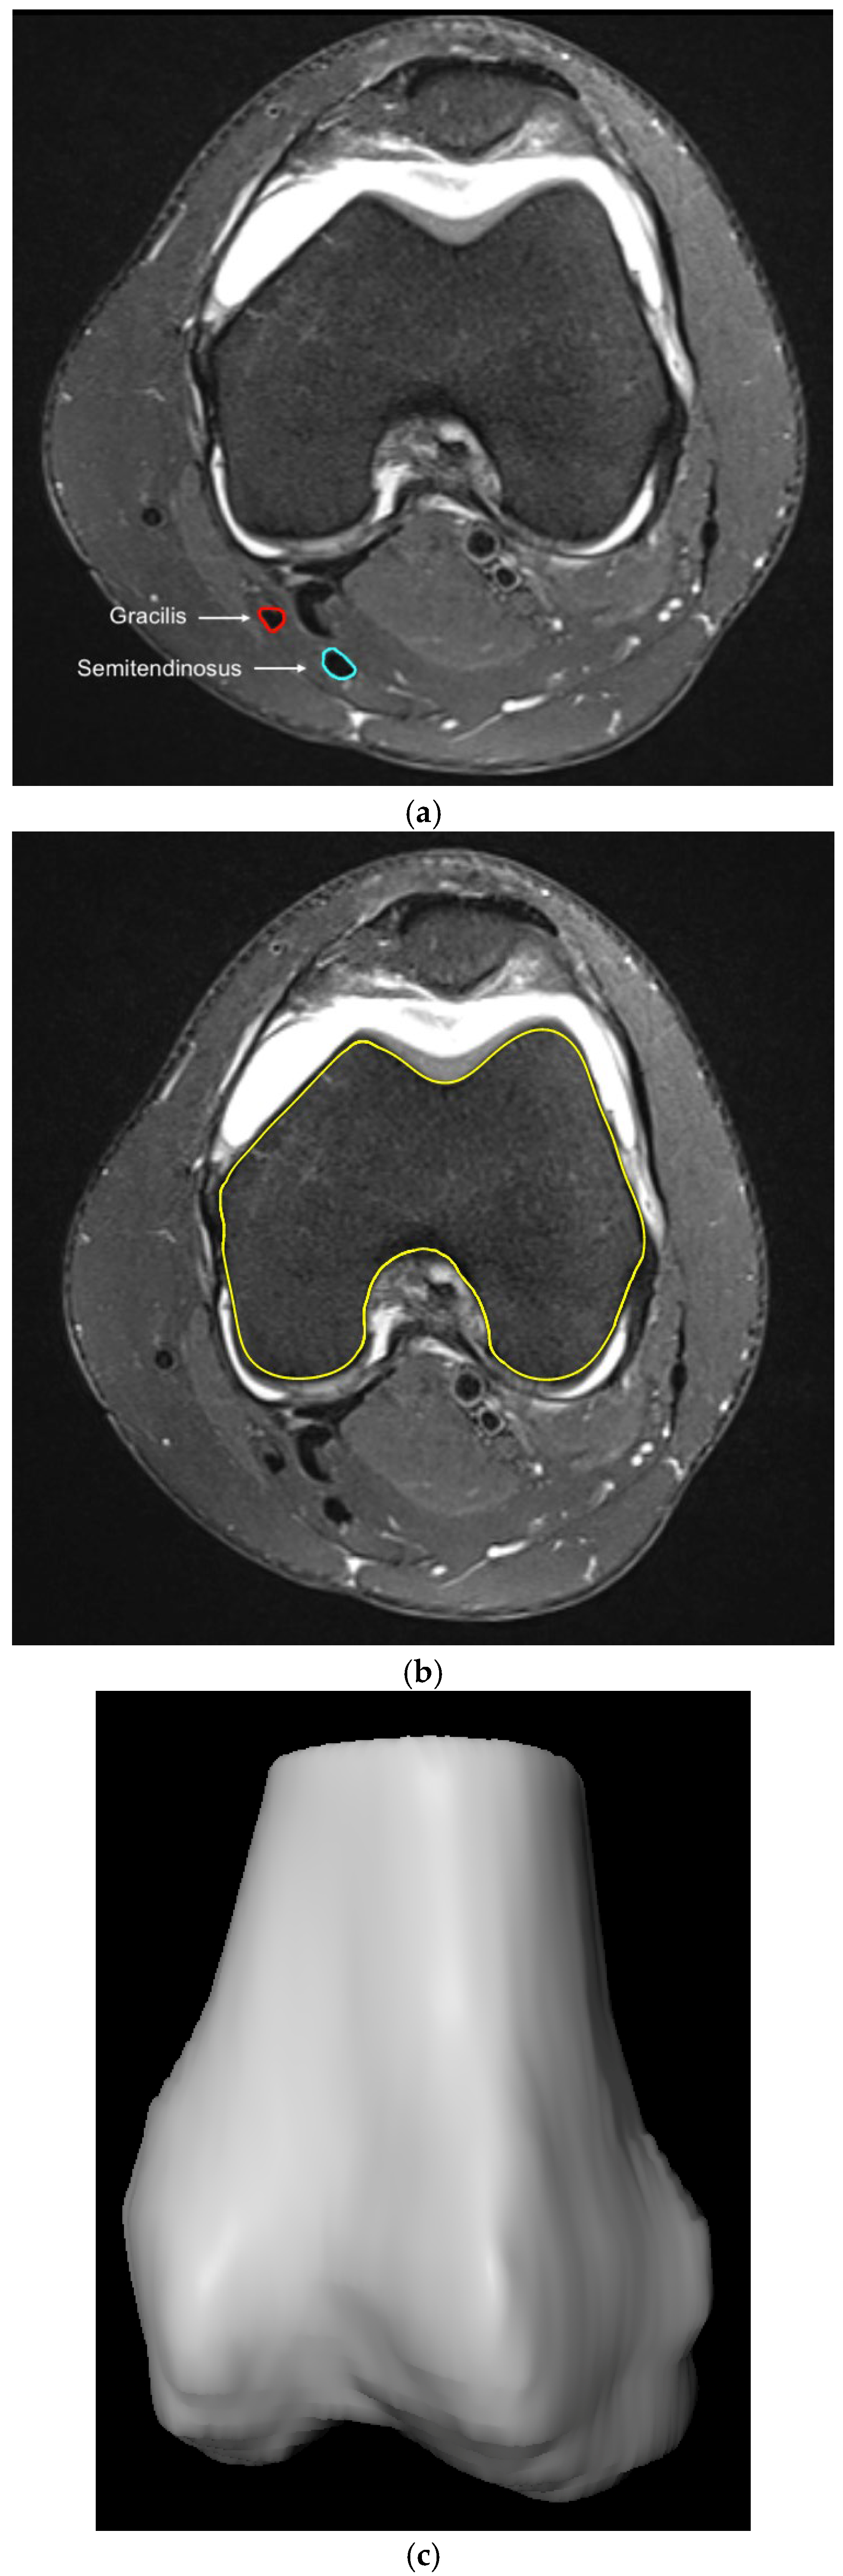

2.2. Methodological Approach